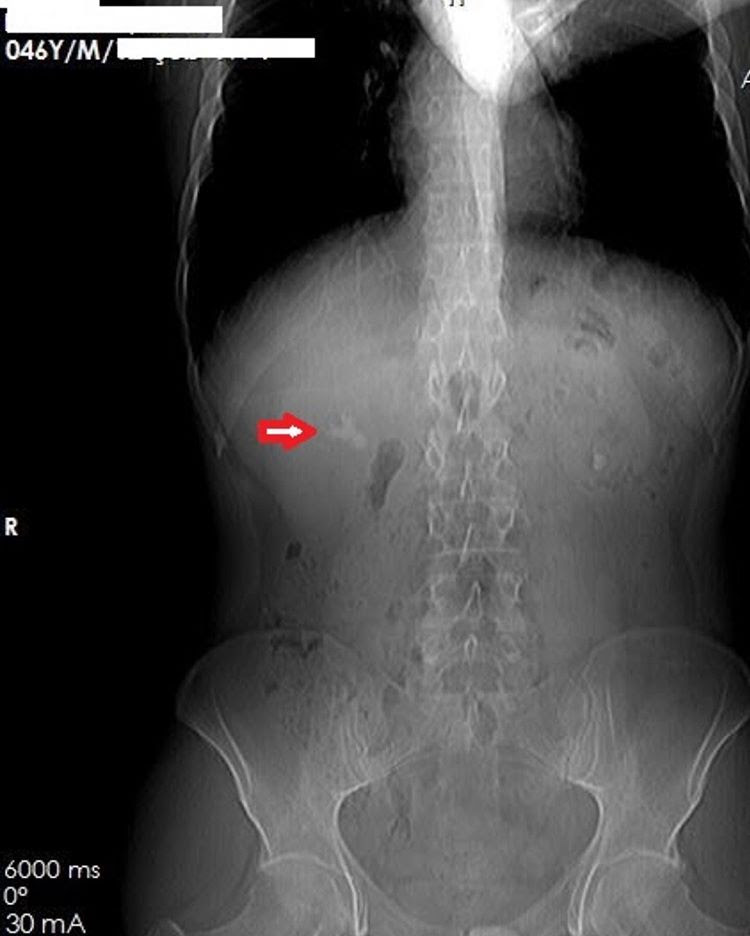

Perkütan Nefrolitotomi (PCNL) (KAPALI BÖBREK TAŞI AMELİYATI)

Böbrekte 20 mm ve üzerinde veya ESWL ile kırılamayan daha küçük ve böbreğe zarar veren taşlar için uygulanan kapalı ameliyat metodudur. Bu yöntem anestezi altında anestezi altında ultrason veya XR kılavuzluğunda böbreğe 1 cmlik bir delikten girilerek kameralı cihazlarla taşa ulaşılması, aşın holmium lazerle parçalanması ve tüm parçaların dışarıya alınması esasına dayanır. En önemli avantajı 1-2 gün içerisinde hastanın eve dönebilmesidir. Açık ameliyatlarda hastanın ayağa kalkması bile 1-2 haftayı buluyordu. ayrıca vücudu taşıyan kaslar kesildiği için kalıcı asimetri ve ciddi yara izi kalıyordu.